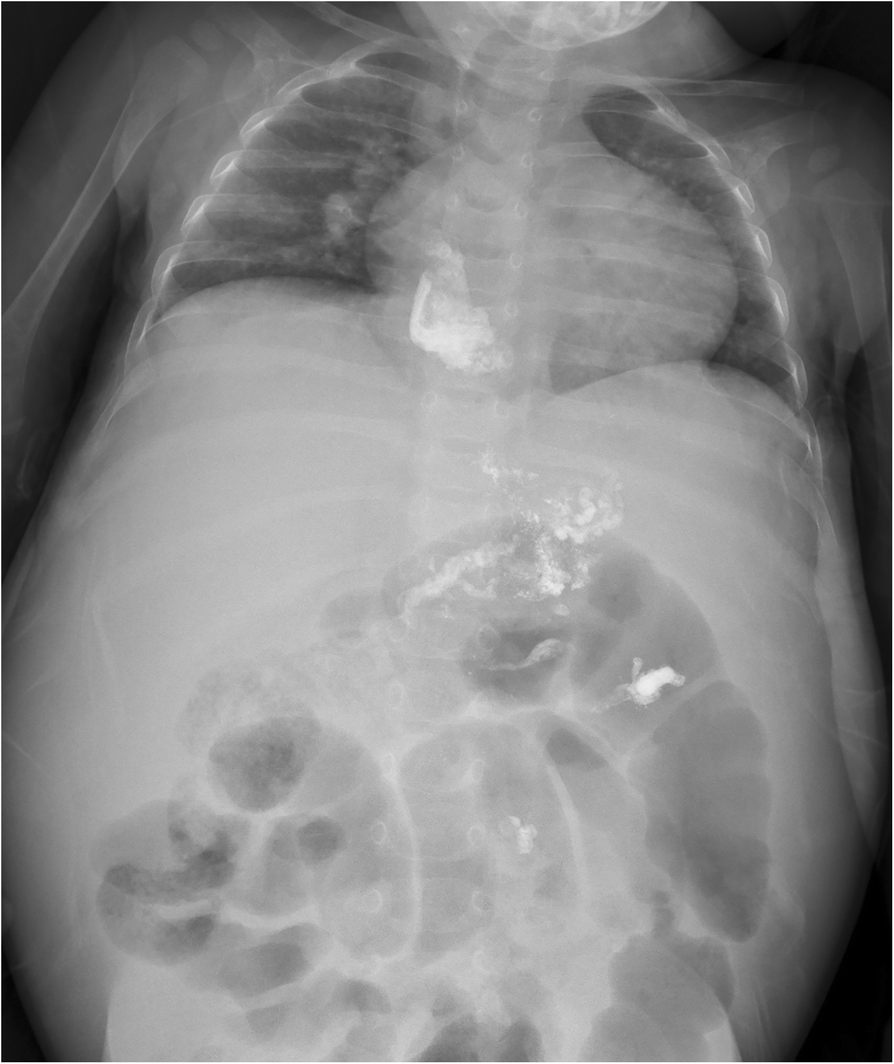

Computed Tomographic Portography with Esophageal Variceal Measurements Endoscopic Esophageal Variceal Sclerotherapy Web endoscopic therapies for varices aim to reduce variceal wall tension by obliteration of the varix. Web endoscopic variceal ligation (evl) was developed in an effort to find an effective endoscopic treatment for. Web endoscopic sclerotherapy is an accepted treatment for bleeding esophageal varices, but it is associated with. Web the following describes an historical overview of endoscopic treatment for. Endoscopic Esophageal Variceal Sclerotherapy.